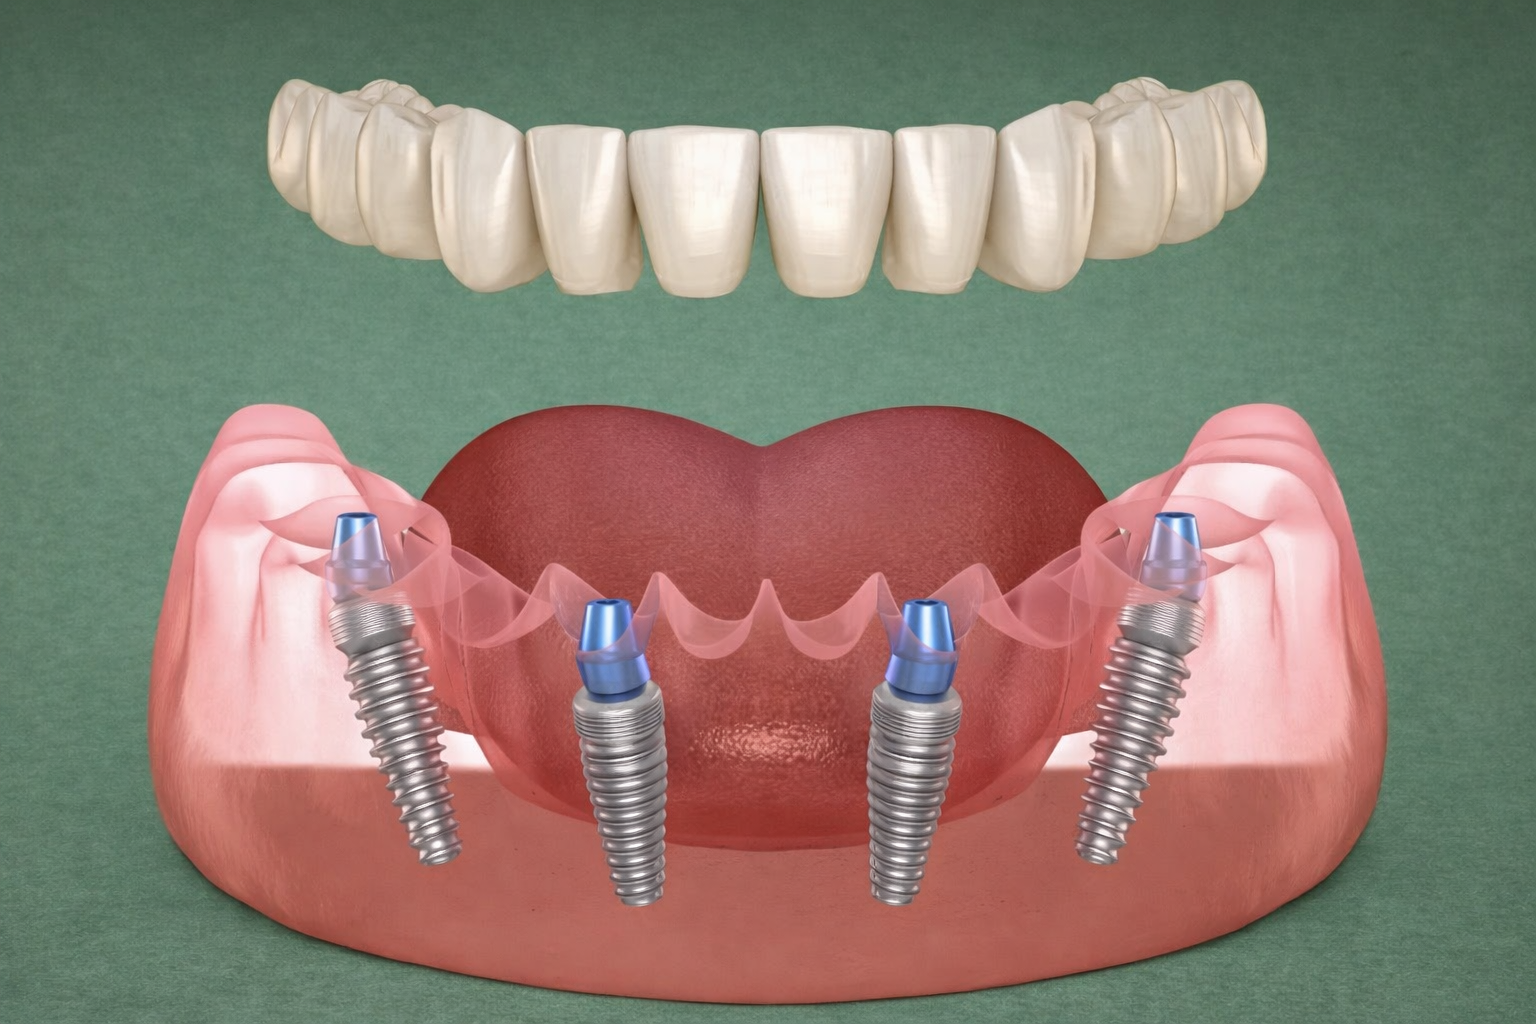

ما هي تقنية All-on-4؟

All-on-4 هي تقنية زراعة لفك كامل حيث يتم دعم مجموعة أسنان ثابتة بواسطة أربع زرعات لكل فك. غالبًا توضع الزرعتان الأماميتان بشكل عمودي، بينما قد تُوضع الزرعتان الخلفيتان بزاوية لتحسين الاستفادة من العظم وزيادة الثبات— ما قد يقلل الحاجة لزراعة عظم كبيرة لدى بعض الحالات.

الهدف واضح: استبدال كامل أسنان الفك (المفقودة أو المتضررة) بحل ثابت ووظيفي بمظهر طبيعي وإحساس آمن.

1) تصاميم زرعات تُستخدم في الفك الكامل

- زرعات خلفية بزاوية (جزء أساسي من مفهوم All-on-4)